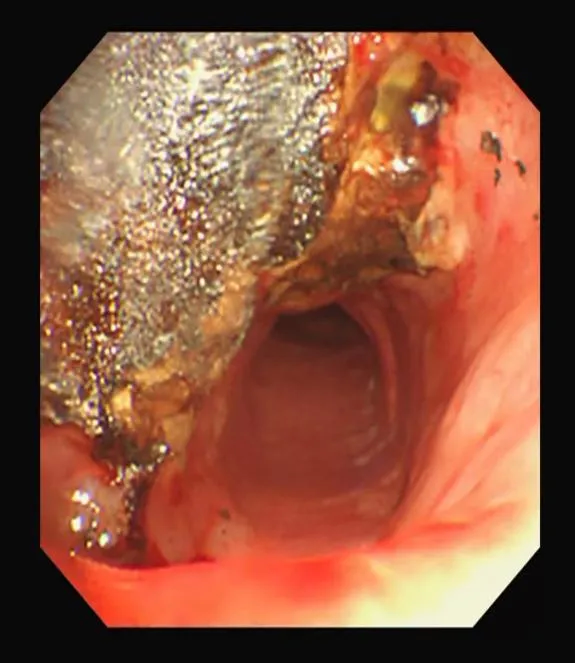

这是一场与时间的赛跑,呼吸与危重症医学科李涛主任医师团队第一时间在局麻下行气管镜急诊探查,见患者声门下2CM气管内肿瘤新生物完全梗阻,管腔呈“一线天”状,他小心翼翼的在高频电下消融+圈套部分肿瘤病灶,使得患者呼吸困难显著改善,血氧饱和度回升到正常值,紧接着予以二次手术。

在麻醉科的全力协助下,李涛主任团队成员各司其职,密切配合,手术过程紧张而有序,联合多种呼吸介入操作电光火石之间,彻底清除梗阻新生物,同时完美的植入了气管支架,完全打通了阻塞气道,林先生的喘憋症状得到了完全缓解,手术的成功,为林先生后续进一步的全身治疗奠定了坚实的基础。